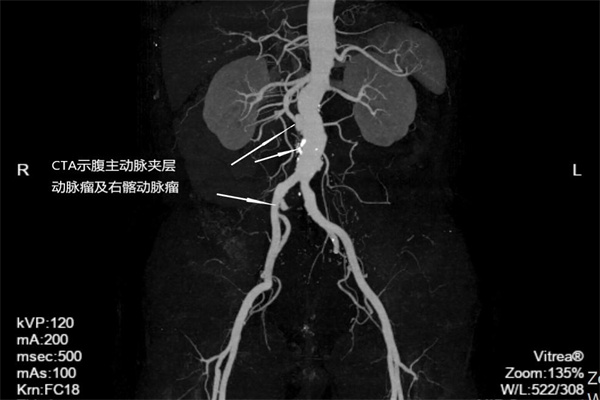

57歲的張叔在查體時(shí)發(fā)現(xiàn),腹主動(dòng)脈夾層動(dòng)脈瘤及右髂動(dòng)脈夾層動(dòng)脈瘤,破裂的風(fēng)險(xiǎn)很高。神經(jīng)內(nèi)科介入醫(yī)學(xué)科團(tuán)隊(duì)考慮到傳統(tǒng)開(kāi)腹手術(shù)創(chuàng)傷大,術(shù)后并發(fā)癥多,決定為張叔實(shí)施腔內(nèi)隔絕術(shù)。

圖2:術(shù)前腹主動(dòng)脈CTA